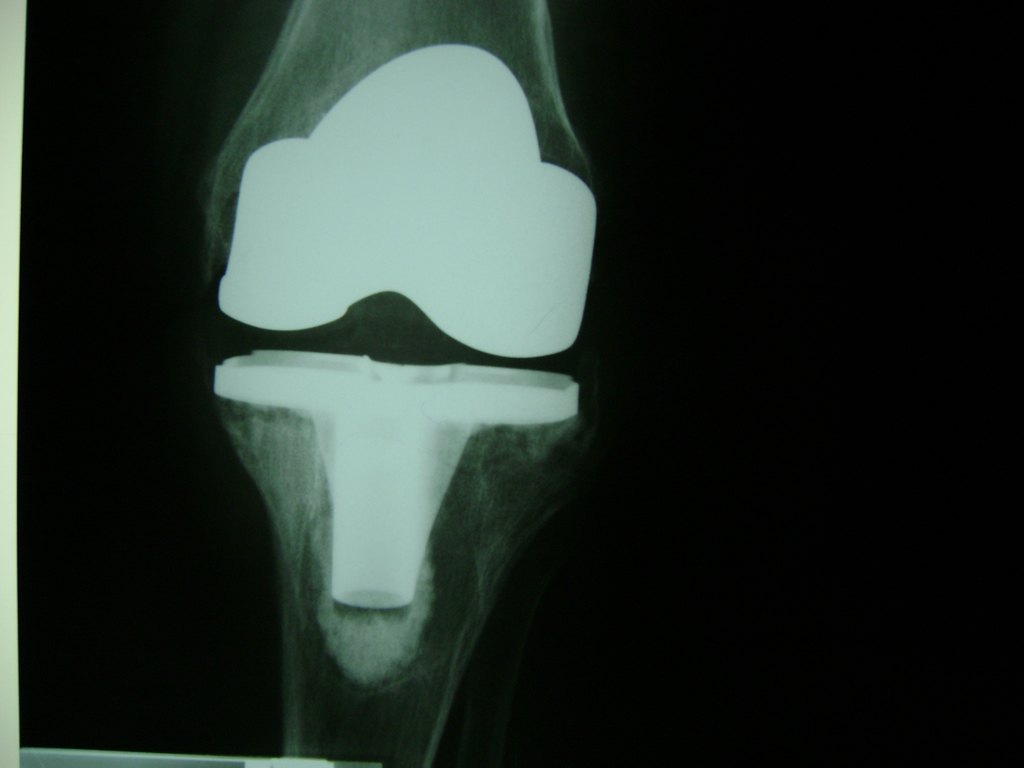

Cirugías de Húmero - Rodilla

La artroscopia de rodilla es un cirugía en el cual la estructura interna de la articulación es examinada ya sea para realizar un diagnostico o para realizar un tratamiento, este procedimiento se realiza utilizando un instrumento parecido a un pequeño tubo llamado artroscopio.